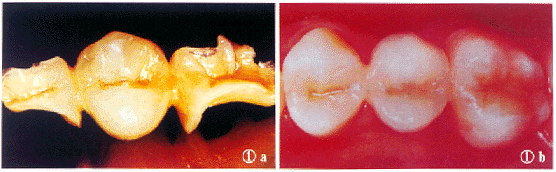

临床应用超瓷材/纤维冠桥制作完成嵌体19件,全冠312件,贴面32件,固定桥73件。观察3~24个月(平均13个月),修复体固位良好,色泽协调一致,与基牙边缘高度密合,龈缘无炎症,咀嚼功能正常,无过敏、疼痛(图1,2)。2个前牙冠和1个前磨牙冠松脱,经重新粘结后效果良好;1个后牙嵌体及2副后牙固定桥牙尖崩缺,经超瓷材修补后效果良好。固定桥无折断现象。

图1 a.粘结前的嵌体桥 b.粘结后的嵌体桥

图2 a.超瓷材/纤维冠桥修复前 b.超瓷材/纤维冠桥修复后